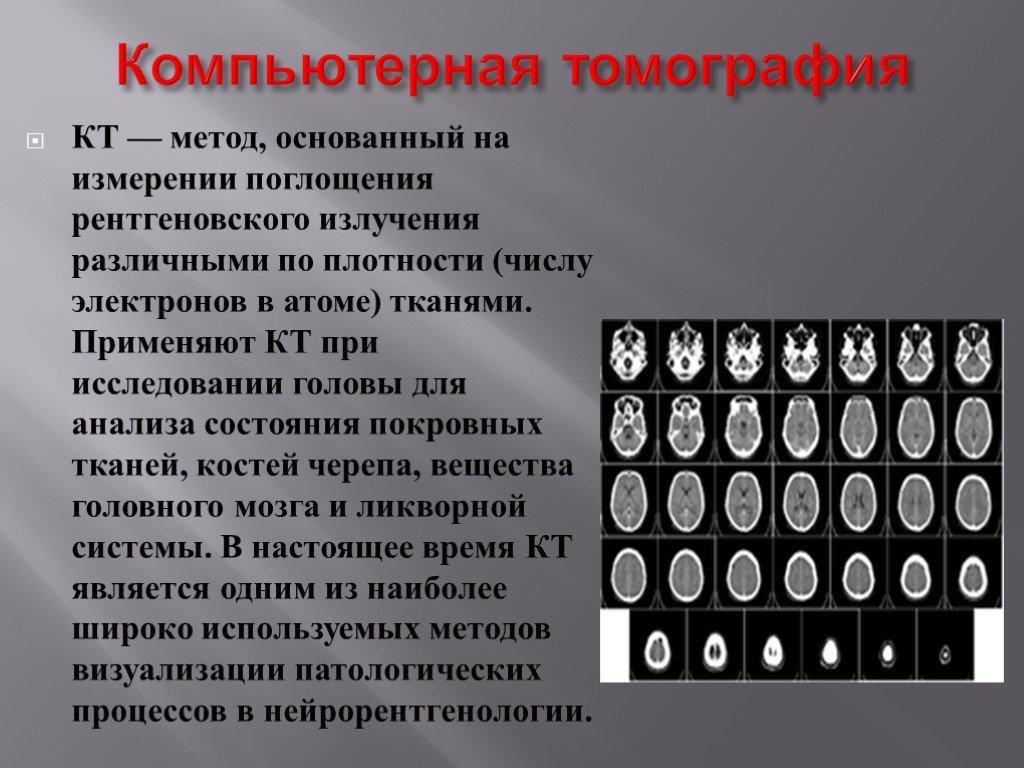

Компьютерная томография в неврологии презентация - 86 фото